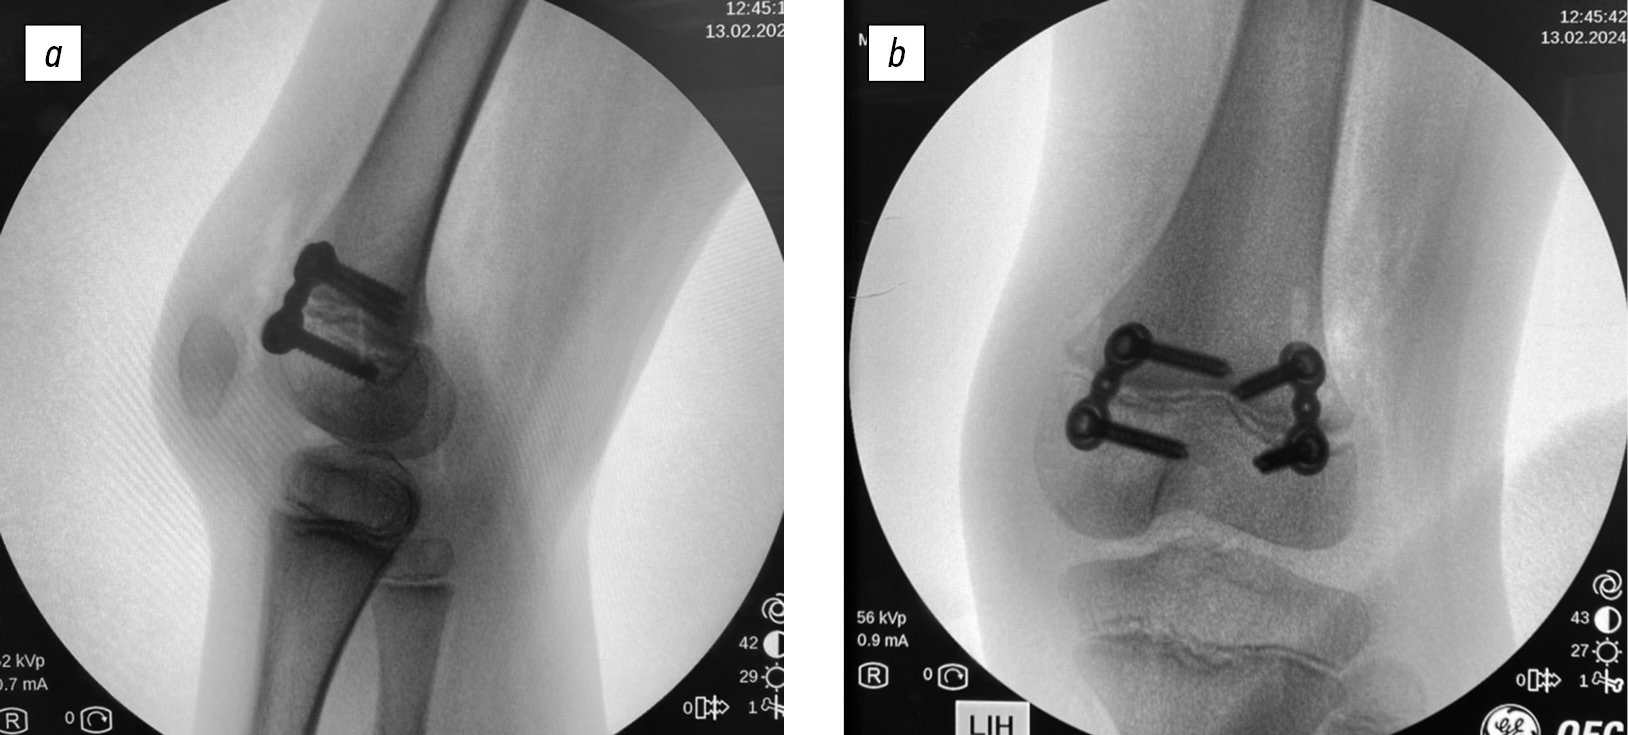

Temporary hemiepiphysiodesis, also called the guided growth technique, involves placing metal implants in the anterior metaphyseal–epiphyseal region of the distal femur. This approach allows for temporary deceleration of growth in this zone, thereby enabling flexion deformity correction. In 2001, the method was first described by Kramer and Stevens [46]. The authors used staples in patients with neuro-orthopedic condition and observed a decrease in KFC from 0° to 11° within 1.5 years after surgery. However, loosening of the staples was noted in some cases. In 2008, Klatt and Stevens [47] modified the technique by introducing the use of plates with screws, which eliminated the previously reported complication (Fig. 3). The efficacy of the technique has been confirmed by several subsequent studies. Al-Aubaidi et al. [39] reported an average KFC correction rate of 0.3° per month using plates, with a mean correction duration of 20 months. At the time of plate removal, the residual contracture averaged 10° (ranging from 0° to 30°), whereas the initial preoperative deformity was 10°–40°. In a study by Stiel et al. [48], the average correction rate of KFC was 0.2° per month. The mean correction period was 38 months, with a residual contracture of 11° (from a preoperative range of 10°–50°). However, in some children with CP, the use of plate-and-screw constructs was associated with intermittent anterior knee pain. To minimize this complication, Kay et al. [49] proposed a percutaneous technique using cannulated screws. This approach decreased the incidence of persistent pain syndrome, minimized the invasiveness of the procedure, and facilitated earlier verticalization of patients. Scientific data do not report recurrences of KFC following temporary hemiepiphysiodesis; however, studies by Al-Aubaidi et al. [39] and Stiel et al. [48] noted KFC recurrence in patients with significant remaining growth potential.

Fig. 3. Radiographs of the knee joint after temporary anterior distal femoral hemiepiphysiodesis: a, lateral view; b, anteroposterior view.

Temporary anterior distal femoral hemiepiphysiodesis is the preferred surgical method for correcting KFC in patients with open growth plates and CP. However, it should be considered that this surgical technique targets the osseous component of the deformity, whereas in patients with CP, KFC is primarily caused by hamstring muscle shortening, particularly in younger children. Therefore, given the pathogenesis mechanism, in this group of patients, it is more appropriate to correct the contracture through soft tissue surgery. In contrast, this method is ineffective in older patients (with closed growth plates), in whom bony changes in the knee joint have already begun.